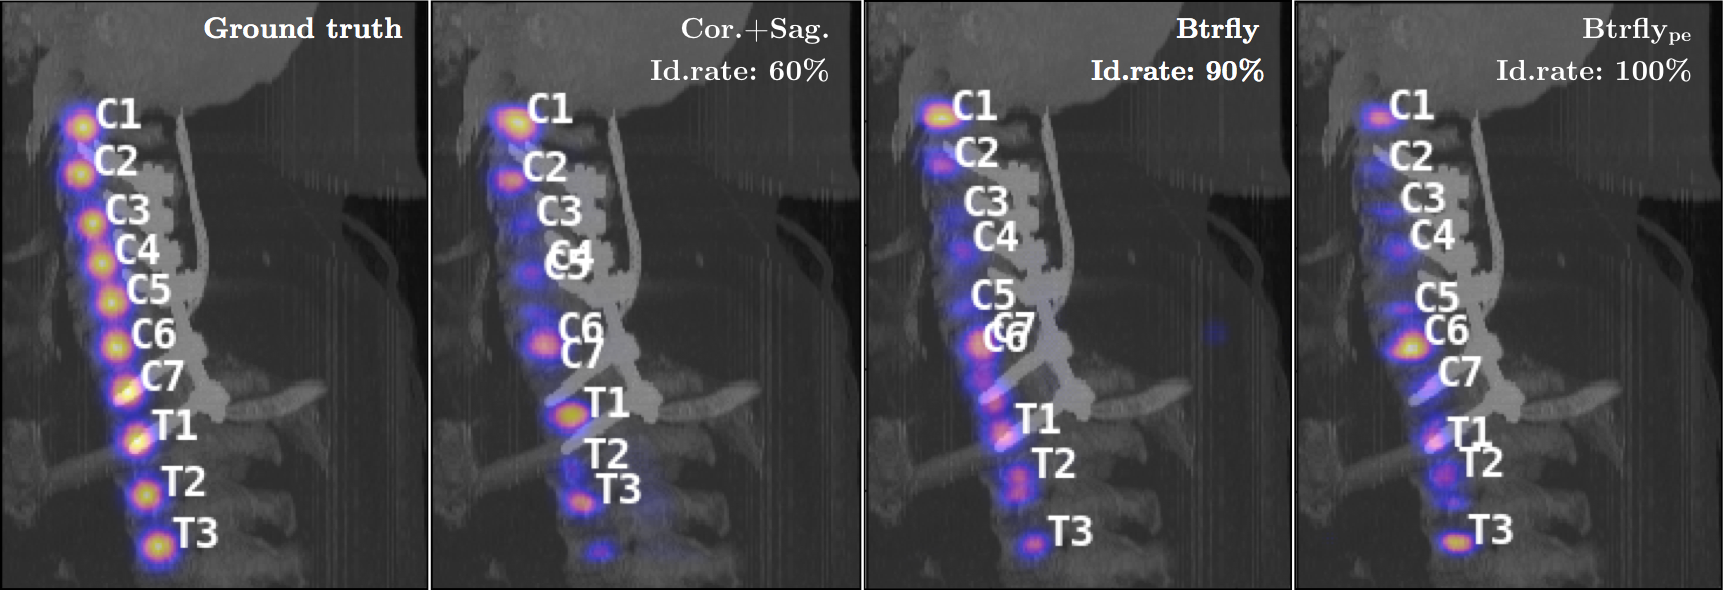

Evaluation & discussion. For evaluating the performance of our network with prior work, we use two metrics defined in [2] namely, the identification rates (id. rate, in %) and localisation distances (d & d, in ). We report the measures in Table 1. It lists the performance of three variants of our network and compares them with several recent approaches. We address three main questions through our experiments: (1) Why the butterfly shape? Compared to Cor.+Sag. nets, performance improves with the Btrfly net. This is because the combination of views causes the predictions of the Btrfly net to be spatially consistent across views. We also observe a 6% improvement in the id.rate over a naive 3D FCN (DI2IN). (2) Why the adversarial prior-encoding? In addition to the advantages of the Btrfly net, the Btrfly net possesses adversarially encoded spatial distribution of the vertebrae. This results in about a 4% increase in the id. rate. Compared to the prior work, Btrfly net achieves state-of-art measures in both the metrics, and it does so by being a single network trained end-to-end. (cf. Fig. 4) (3) Relation to latent-space learning? EB- is more flexible than the AEs in [4, 5] as it learns from scratch and converges to a latent manifold best representing the true as well as generated data. The reconstruction capability of the AE for a generated sample is of interest. Using the output of the AE instead of Btrfly, we achieve an id.rate of 75% with a d of , indicating the AEs’ capability of transferring the learning from true to contrastive samples.